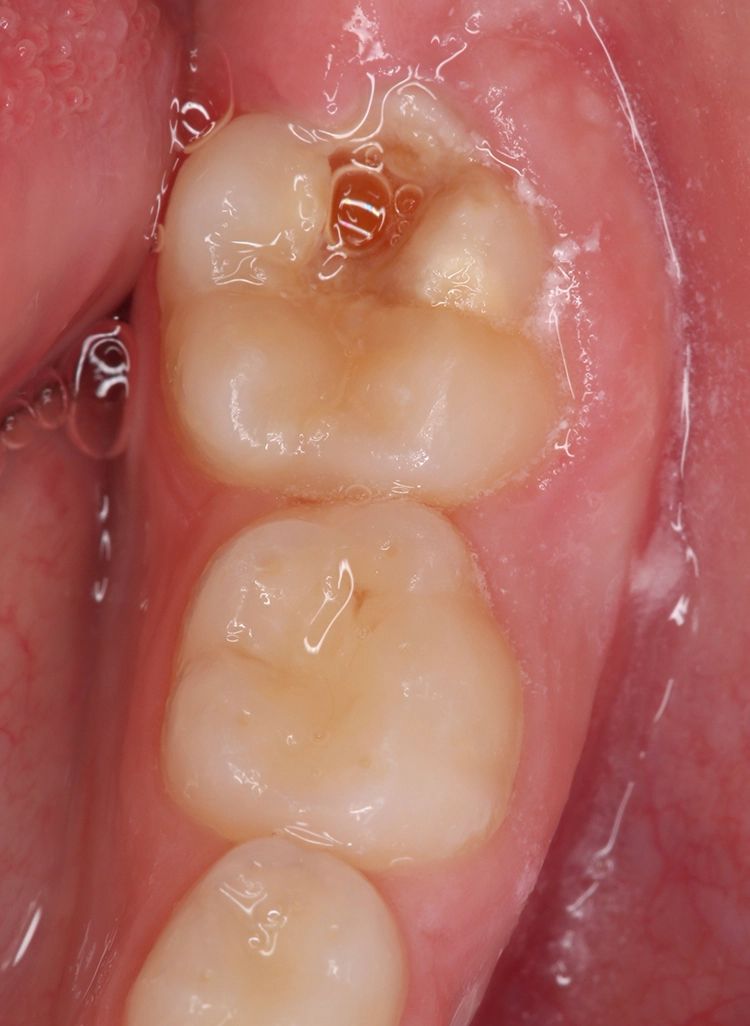

Bekes/BoukhobzaAbb. 4: Abdeckung eines MIH-Molaren mit einem Glasionomerzement.

Glasionomerzemente sind ideal zur initialen und provisorischen Abdeckung von durchbrechenden Zähnen und zur Vermeidung eines weiteren Zahnhartsubstanzverlustes (Abb. 4). Die einfache Handhabung, aufgrund des Wegfalls von Konditionierungsschritten, erleichtert die Anwendung besonders bei eingeschränkter Kooperation des Patienten. Aufgrund der niedrigen Biegefestigkeit und minimalen Abrasionsstabilität eignet sich dieses Material jedoch nicht als definitives Restaurationsmaterial von MIH-Molaren, da gerade bei großflächigen, höckerersetzenden Bereichen keine adäquate Stabilität gewährleistet wäre.

Seit Einführung der ersten Glasionomerzemente in den 1970er-Jahren wird eine vorteilhafte Fluoridfreisetzung durch dieses Material behauptet. Die aktuelle Datenlage zeigt jedoch, dass die Abgabe von Fluoridionen klinisch eine eher untergeordnete Rolle spielt, da diese Wirkung bereits nach einigen Tagen auf ein vernachlässigbares Niveau sinkt [13].